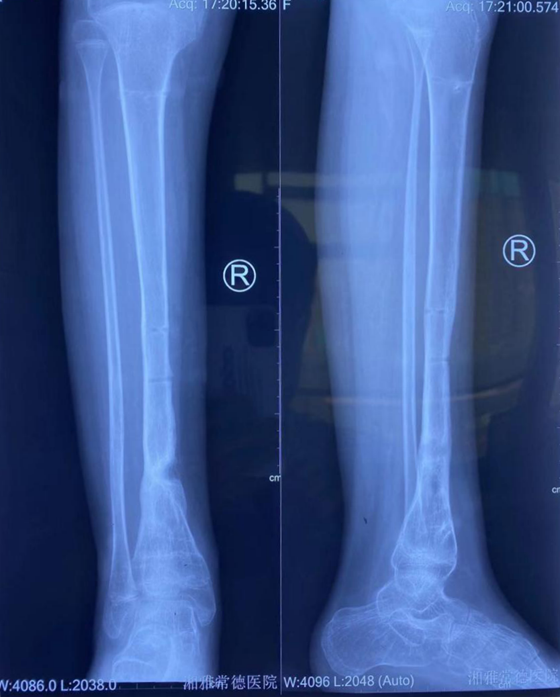

由于胫骨下段血运较差,软组织抗感染能力很弱,且靠近病变靠近骨骺端,该处慢性骨髓炎的治疗较为困难。加之,蓓蓓存在畸形骨缺损、骨不连,将来踝关节功能障碍,畸形发育的风险高,如果感染控制不了,仍然有迁延不愈的风险。创伤组组长王穗源副主任医师组织了全科讨论,为蓓蓓“量身定制”了手术方案。1月11日,王穗源副主任医师主刀为蓓蓓行骨髓炎病灶清除,Ilizarov外固定技术辅以抗生素硫酸钙骨髓泥填充诱导成骨技术,畸形矫正,诱导成骨一步到位。

术后胫骨开始愈合,初步具有支撑下肢活动的能力